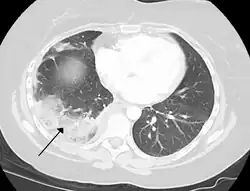

Tissue death of the lung due to a pulmonary embolism

A pulmonary embolism is a blood clot that becomes lodged in the pulmonary arteries. The majority of emboli arise because of deep vein thrombosis in the legs. Pulmonary emboli may be investigated using a ventilation/perfusion scan, a CT scan of the arteries of the lung, or blood tests such as the D-dimer.[74] Pulmonary hypertension describes an increased pressure at the beginning of the pulmonary artery that has a large number of differing causes.[74] Other rarer conditions may also affect the blood supply of the lung, such as granulomatosis with polyangiitis, which causes inflammation of the small blood vessels of the lungs and kidneys.[74]